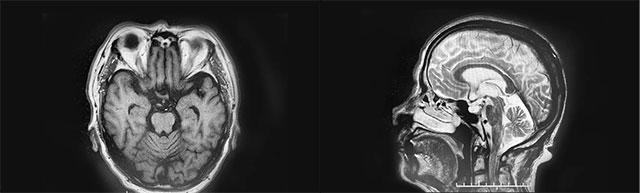

▲ 患者腦體積縮小,腦溝增寬加深,萎縮明顯

經(jīng)磁共振檢查,鐘老伯有雙側(cè)額葉皮層下微腔隙缺血灶,腦萎縮明顯。李振并主任介紹,鐘老伯具有帕金森病典型的運動癥狀表現(xiàn),但帕金森病和帕金森綜合征,名字上只是病和綜合征之別,卻不能簡單地混為一談。